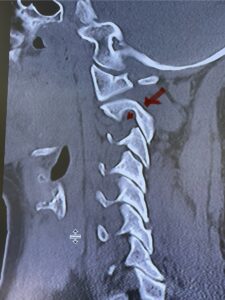

Cervical x-rays revealed a significantly increased atlanto-axial interval (Fig. 5) On review of her imaging studies it was noted that the right C2 isthmus was very thinned by the vertebral foramen (Figs 6a, b, and c) which would make an attempt at placing a C2 pars screw dangerous. A decision was made to perform an occipital-cervical fusion because only possible unilateral fixation and an extensive C1 laminectomy to be performed eliminating a fixation point if a more traditional C1-C2 was performed. Even if C1 lateral mass screws were able to be placed one could only perform a unilateral screw construct fixation to C2. We performed an occipital cervical fusion down to C4 to get enough inferior fixation and C1 laminectomy. The decompression went well. We placed a left unilateral pars screw and bilateral C3 and C4 lateral mass screws. We placed three 12 mm screws in the midline keel (Fig. 7). Postoperatively the patient had all around improvement in her symptoms and did not qualify for rehab. Her post op films at 6 weeks (Fig. 8)

Fig. 6c: Axial cervical CT scan demonstrating a very thin right C2 isthmus (red arrow) compared to left side.